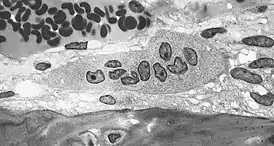

Резорбция костной ткани (разрушение, рассасывание кости, остеолиз) происходит при участии гигантских многоядерных клеток, так называемых остеокластов, которые также имеют большое количество лизосом, митохондрий и вакуолей.

Остеокласт — это основная клетка, участвующая в процессе резорбции кости. При активизации этих клеток у них появляется функциональная зона — «гофрированный край», или «щёточная каёмка». Гофрированный край представляет собой спирально-скрученную мембрану клетки с множественными цитоплазматическими складками, который обращён в сторону развивающегося процесса резорбции, и является местом активного окисления тканей.[1]:26-28 Группа остеокластов растворяет минеральный компонент кости, а также гидролизует органический матрикс. Разрушение кости начинается с прикрепления остеокласта к минерализованной костной поверхности «гофрированным краем», через который выделяются гидролитические ферменты и протоны, а также различные интегрины (α₁, αᵥ, β₁, β₃), участвующие в растворении кости.[1]:28 Другие клетки, принимающие участие в резорбции костной ткани — это моноциты и макрофаги. Они взаимодействуют с костной тканью посредством фагоцитоза и хемотаксиса, в большинстве случаев действуя как «уборщики мусора». Помимо фагоцитарной активности продуцируются цитокины (ИЛ-1, ИЛ-1α, ИЛ-1β, ФНО-α и др.) влияющие на активизацию коллагеназ, разрушающих белковый матрикс. Кроме того, моноциты и макрофаги рассматриваются многими учёными как предшественники остеокластов.[1]:31-32 Имеются сведения о влиянии лимфоцитов на резорбцию костной ткани посредством секреции ФНО-β, а также через 1,25-дигидроксивитамин D и ПТГ, к которым лимфоциты имеют рецепторы.[1]:32